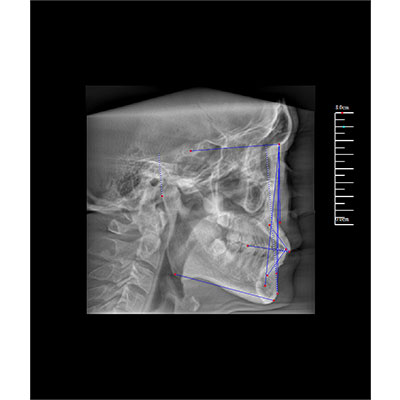

該款牙科CBCT產(chǎn)品采用動態(tài)平板探測器,獲得三維圖像的同時還具有數(shù)字化全景功能,廣泛應用于口腔頜面外科、正畸科、正頜外科、種植科、牙體科、顳下頜關節(jié)科等術前術后。

專有三維重建算法,可提供任意位置高清斷層影像。

可同時觀察軸向面、冠狀面和矢狀面圖像,方便臨床診斷。